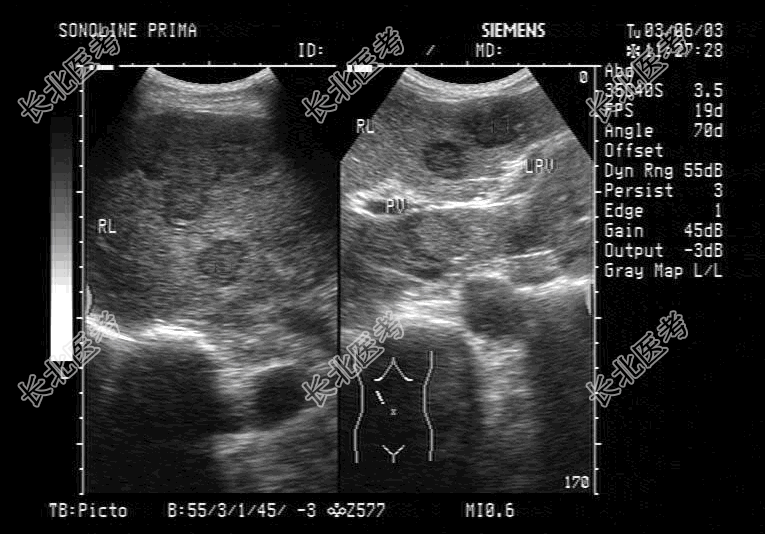

- 单项选择题男,62岁, 直肠肿瘤术后半年。结合超声检查如图,那么诊断为

A、肝硬化

B、转移性肝癌

C、肝囊肿

D、肝脓肿

E、肝血管瘤